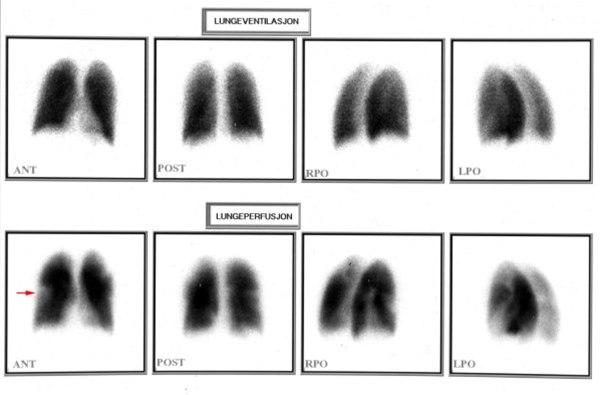

Perfusjons-scintigrafi (blodstrøms-måling) viser manglende gjennomstrømning i venstre lunges overlapp (1)